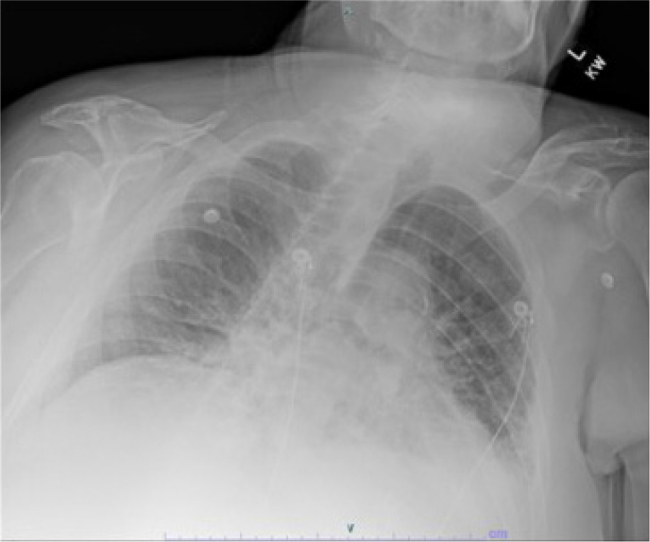

Abstract Image